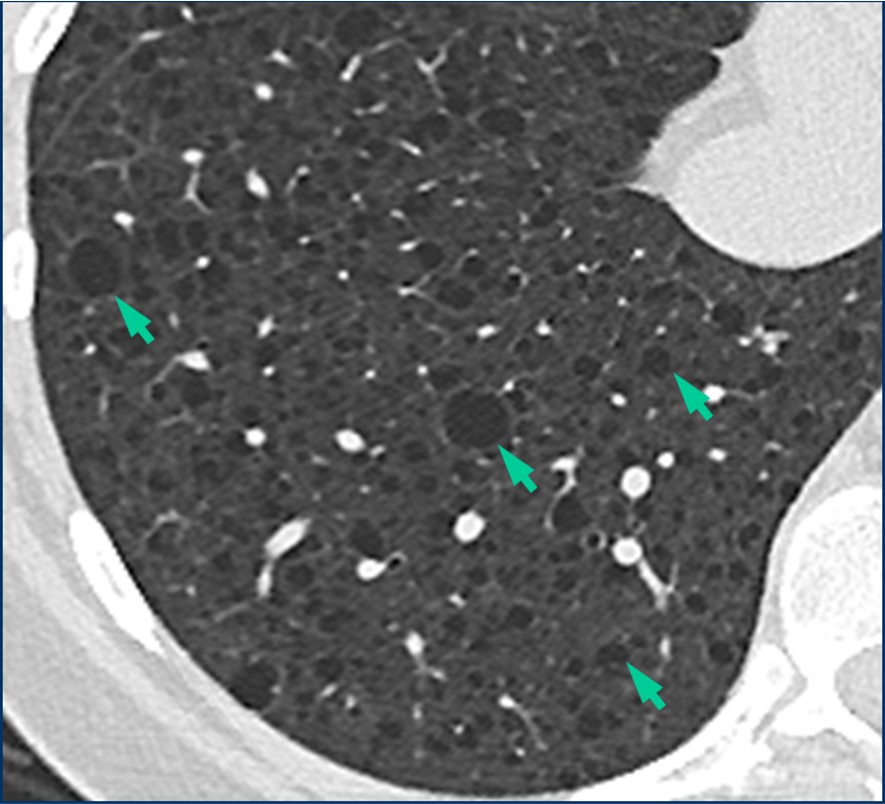

Example

Lacking honeycombing, probable UIP exhibits bronchiectasis and may have histopathologic signs of UIP upon biopsy. Surgical biopsy therefore may aid in IPF diagnosis.3

Note the lack of honeycombing in this image.

HRCT image of possible usual interstitial pneumonia. Reprinted from Fishman‘s Pulmonary Diseases and Disorders. 4th edition 2007. Meltzer EB and Noble PW: Chapter 70, Idiopathic Pulmonary Fibrosis.10 Used with permission from McGraw-Hill Companies. Inc. Copyright © 2007 McGraw-Hill Companies. Inc.